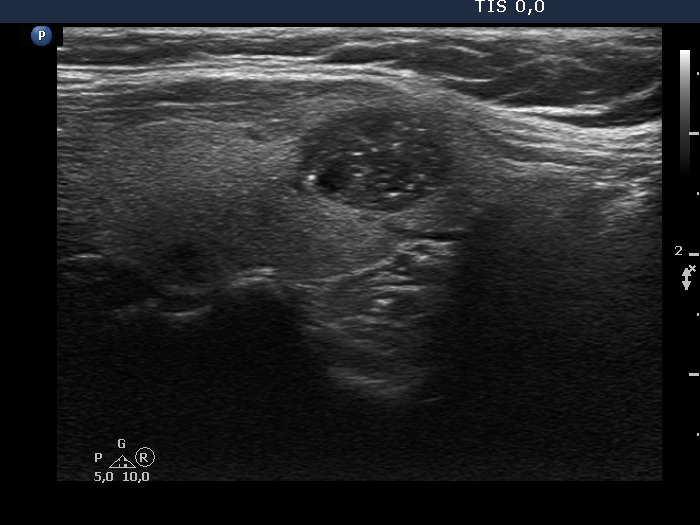

Ultrasonography. The thyroid was echonormal. There was hypoechoic nodule in the left lobe. The nodule had numerous echogenic granules and lines. Video record proved that these are clearly related to ventral cystic areas, therefore these are back wall cystic figures caused by posterior enhancement. The nodule showed taller-than-wide sign.

Comment. This case illustrates why is video clearly superior to still images in analyzing thyroid nodules. Viewing the still image on transverse section (first image in the list), the intranodular echogenic figures seem to be microcalcification. However, video clearly proved the presence of tiny cystic areas ventral to these echogenic figures.